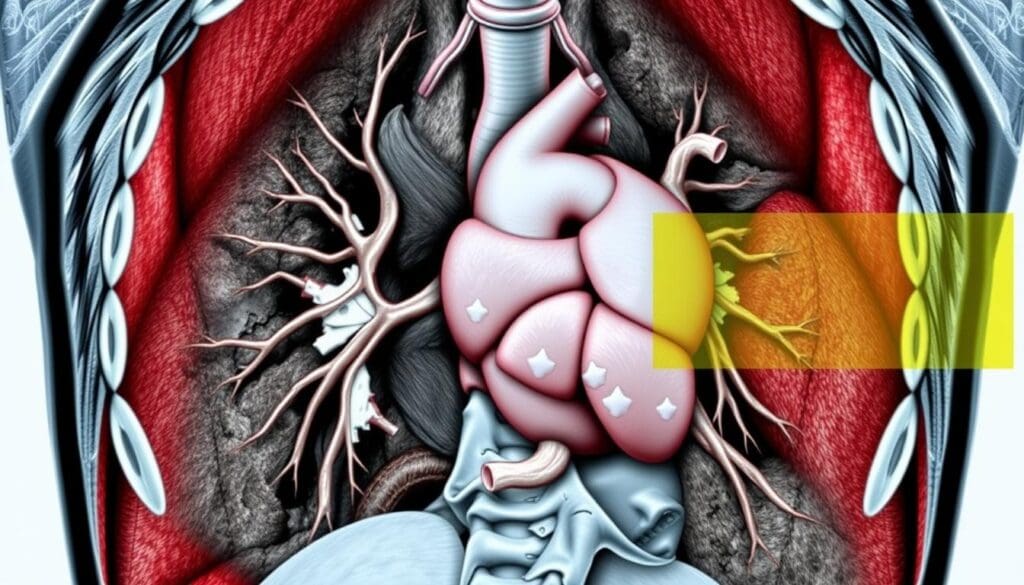

At LivHospital, we use top-notch diagnostic tools for our patients. A chest CT scan gives us detailed pictures of the chest area. Many wonder cat scan on chest what does it show, and it reveals the lungs, airways, heart, blood vessels, bones, and surrounding tissues, helping diagnose infections, tumors, lung diseases, and other conditions.

A chest CT scan gives a detailed look at the chest’s internal parts. It’s key for spotting many chest issues. We’ll see what structures and tissues it shows and how image quality is affected.

Overview of Visible Structures and Tissues

A chest CT scan shows many parts, like the lungs, heart, esophagus, and more. It’s great for finding lung problems, heart issues, and other diseases. It can also check the esophagus for problems, but it depends on a few things.

What Organs Does a Chest CT Scan Show?

A chest CT scan is a powerful tool for diagnosing. It shows many organs and structures in the chest. This helps doctors find and treat different health issues.

Heart and Major Blood Vessels

A chest CT scan also looks at the heart and major blood vessels. It checks the heart’s size and shape, and the health of the coronary arteries. This is key for spotting heart diseases.

Mediastinal Structures

The mediastinum, between the lungs, holds important structures like the esophagus, trachea, and lymph nodes. A chest CT scan examines these for any issues, like swelling or masses.

Bones and Chest Wall

A chest CT scan also looks at the bones and chest wall. It checks the ribs, vertebrae, and sternum, along with soft tissues. This is vital for spotting fractures, degenerative changes, or bone problems.

In summary, a chest CT scan gives a detailed look at the chest’s organs and structures. This includes the lungs, heart, mediastinal structures, and bones. Such detailed images are essential for accurate diagnosis and treatment planning.